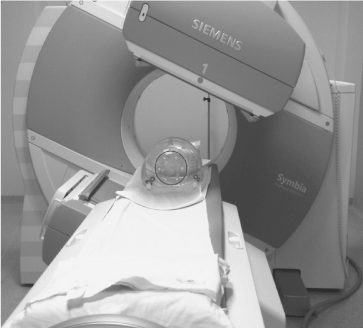

In this study only phantoms were considered. The acquisition set up of the camera is shown in Figure 1.

Figure 1. Acquisition set-up where the six radioactive spheres into the NEMA IEC Body PhantomTM are acquired in the SPECT/CT imaging system.

SPECT/CT scans were acquired on a Symbia T2 gamma-camera (Siemens Medical System, Germany) with a 3 / 8 inch NaI (Tl) detector and medium-energy low-penetration (MELP) collimator, with a sensitivity of about 13.9 cps/MBq (for ME collimators with 67Ga) extracted from factory data sheet. The tomographic projection images were acquired in step and shoot mode, for 64 views over 360° and 30 sec/frame. Zoom of 1, circular radius of rotation of 330 mm (around the phantom surface) and image matrix of 128x128 pixels were set, resulting in a 4.8 mm pixel size image. In acquisition, the energy windows of the two dominant photopeaks of 177Lu [4] were set at 113keV ± 7.5% and 208.4keV ± 7.5%, as also described in Grassi et al [30]. As regards the lower energy photopeak, the TEW scatter correction was employed and the lower scatter window was set in the range from 87.58keV to 104.53keV (using a default window weight of 0.5), while the upper scatter window from 121.47keV to 130.51keV (using a default window weight of 0.9375). With respect to the higher energy photopeak, the DEW scatter correction was employed and the lower scatter window ranged from 171.60keV to 192.40keV (using a default window weight of 0.75) [30].

Following the SPECT acquisition, an X-ray CT scan of the phantom was generated using a 130kV and 30 mAs beam (clinical parameters), and a smooth reconstruction kernel (B08s; Siemens Medical Solution, Germany). The reconstructed slice thickness was set to 5 mm.

Reconstruction of SPECT / CT images and imaging analysis were performed in Siemens E-Soft workstation (Syngo MI, Application version 32B, Siemens Medical Solution, Germany). The images were reconstructed with the proprietary iterative Flash 3D reconstruction algorithm which includes correction for attenuation (based on energy extrapolation of the CT values from the automatically registered SPECT / CT image), compensation for scatter (estimated by means of the multiple energy windows method, and incorporated into the reconstruction) and a full collimator-detector response [30].